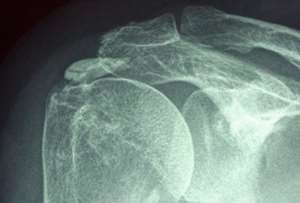

钙化性肌腱炎的介绍和治疗流程

钙化性肌腱炎是指肩袖肌腱中钙质的异常沉积。肩袖是一组环绕肩关节并稳定肩关节的肌腱,当肌腱细胞死亡时,通常会形成疤痕组织,然而,有时候身体会通过产生沉积的钙质来做出反应,钙质的沉积会严重刺激局部肌腱,导致剧烈疼痛。钙质还会在肌腱中形成肿块,限制肩部运动。这些钙质沉积物在X光片上可见,出现时有时候会引起疼痛。钙化性肌腱病通常影响30-50岁年龄段的人。虽然确切病因尚不确定,一般认为其与衰老、磨损、肌腱压力增加以及缺氧有关。症状包括肩部外侧剧烈疼痛,可能会影响睡眠、导致僵硬和难以进行肩部过顶活动。钙化性肌腱病通常经历3个阶段。在初始阶段,钙质沉积物不会明显形成,也不会疼痛。接下来是疼痛的钙化阶段,最后是钙吸收阶段。钙化性肌腱病的诊断需要检查患者的症状、病史和体格检查。钙沉积物通常可以通过X射线、超声波和核磁共振检查看到。钙化性肌腱病通常会自行消退,但病程可能会延长(长达10年)。治疗取决于症状的严重程度、疾病的阶段和沉积物的大小。①、我们医生可能会开止痛药和消炎药来控制疼痛和炎症。②、若口服药物没有作用的话,关节腔注射和针刺沉积物等方式也可以用来减轻肩部的疼痛症状。③、对皮质类固醇和抽吸无反应的病变,可以选择手术作为更明确的解决方案,使用微创关节镜手术从肌腱中去除沉积物。关节镜手术大约需要0.5~1小时。患者通常需住院2-3晚。手术的主要风险是僵硬(肩周炎),一般僵硬最终都会消失。为了避免僵硬,应尽量使用止痛药,并在第二天早晨与理疗康复师一起开始早期活动范围锻炼。不建议使用吊带固定。其他风险包括但不限于感染、皮肤神经损伤和疼痛缓解不完全。通常可以在手术后1-2周开始开车等正常活动,但完全恢复可能需要4-6个月。该肩部钙化性肌腱炎复发极为罕见,但可能发生在另一侧的肩关节。